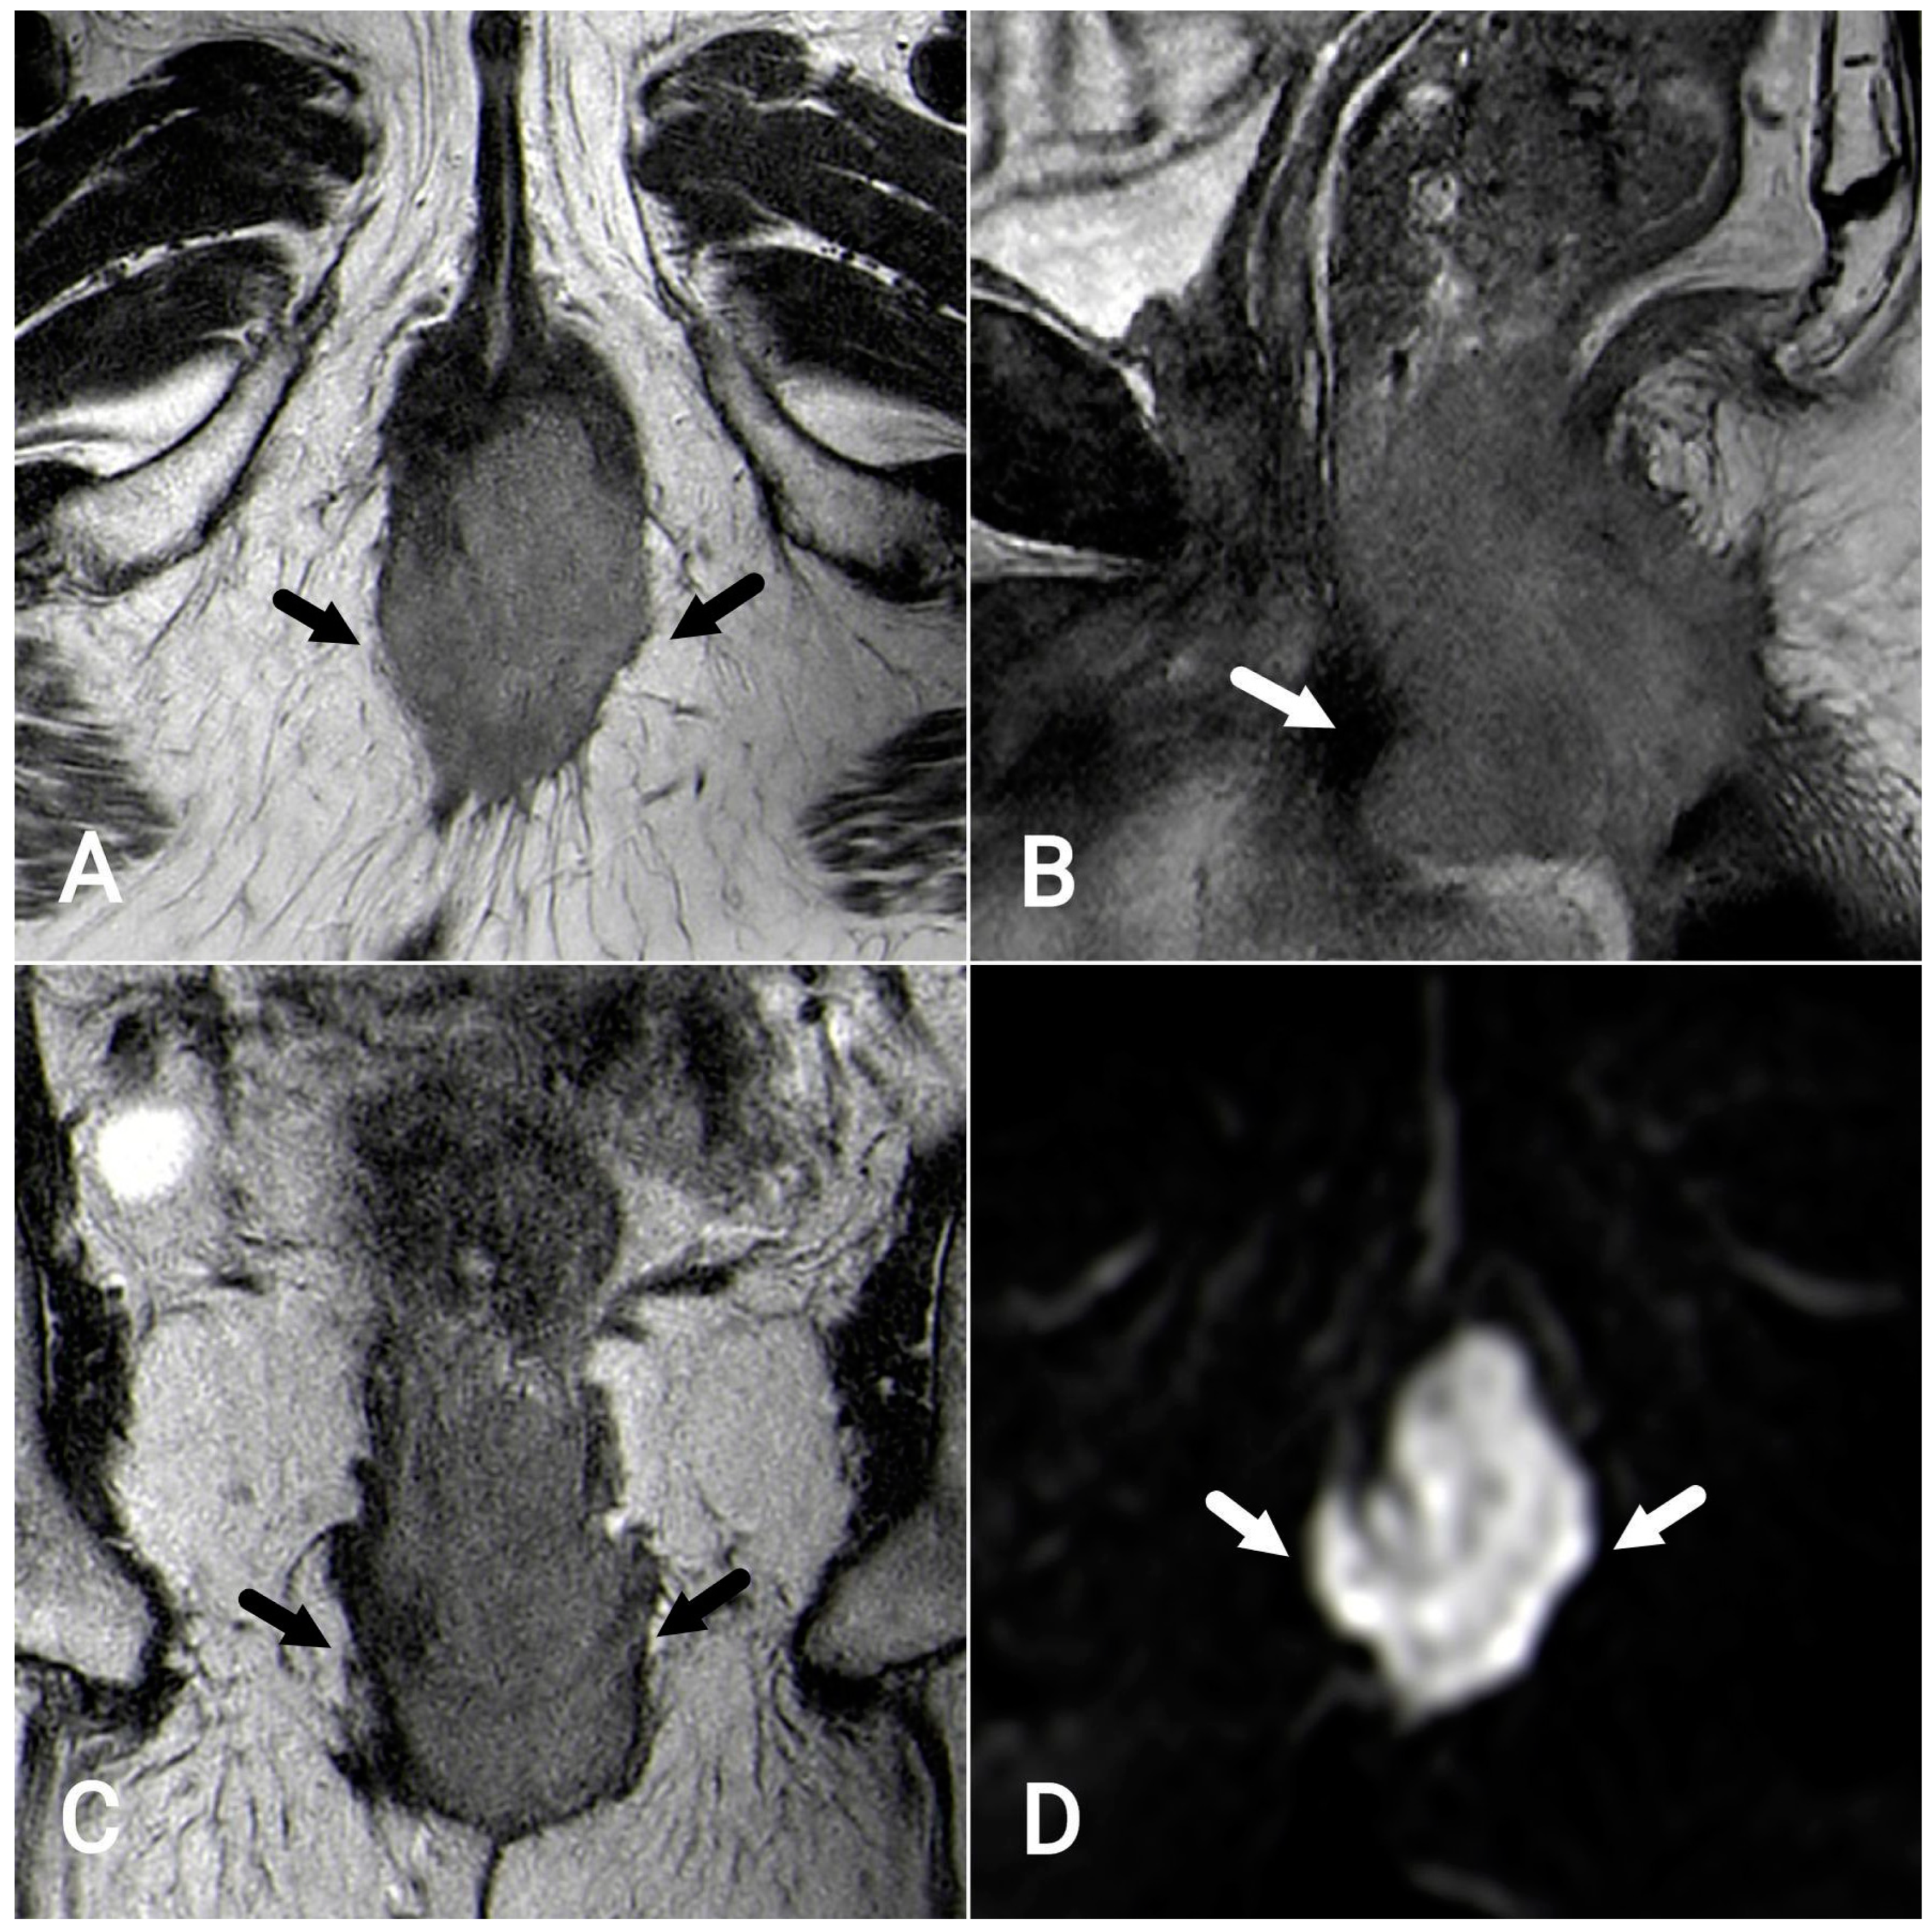

7.1. T-Staging

7.2. N-Staging

Evaluation after Chemoradiation Therapy